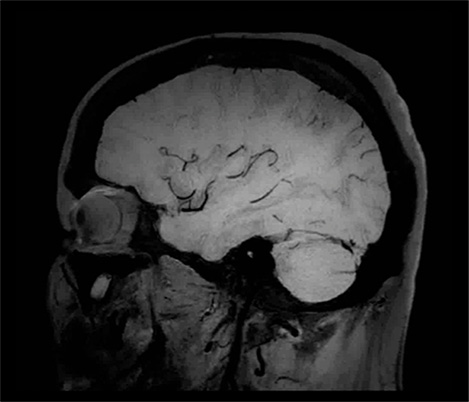

El 70% de los radiólogos consideran que las indicaciones neurológicas son un desafío, sobre todo debido a la falta de técnicas apropiadas de imagenología y visualización¹. Philips tiene como objetivo proporcionar la mejor claridad de diagnóstico posible y orientación terapéutica para todos los pacientes con trastornos neurológicos. Al aprovechar nuestra plataforma digital dStream, este año presentamos un conjunto de estrategias nuevas de imagenología y visualización. Esto puede ayudarlo a resolver preguntas sobre neurología complejas con mayor certeza, así como a desbloquear nuevos territorios neurológicos en aplicaciones neurofuncionales avanzadas. Este es un paso clave para aumentar el diagnóstico neurológico y, en última instancia, impactar más vidas con la RM. ¹ TMTG Market Survey 2016